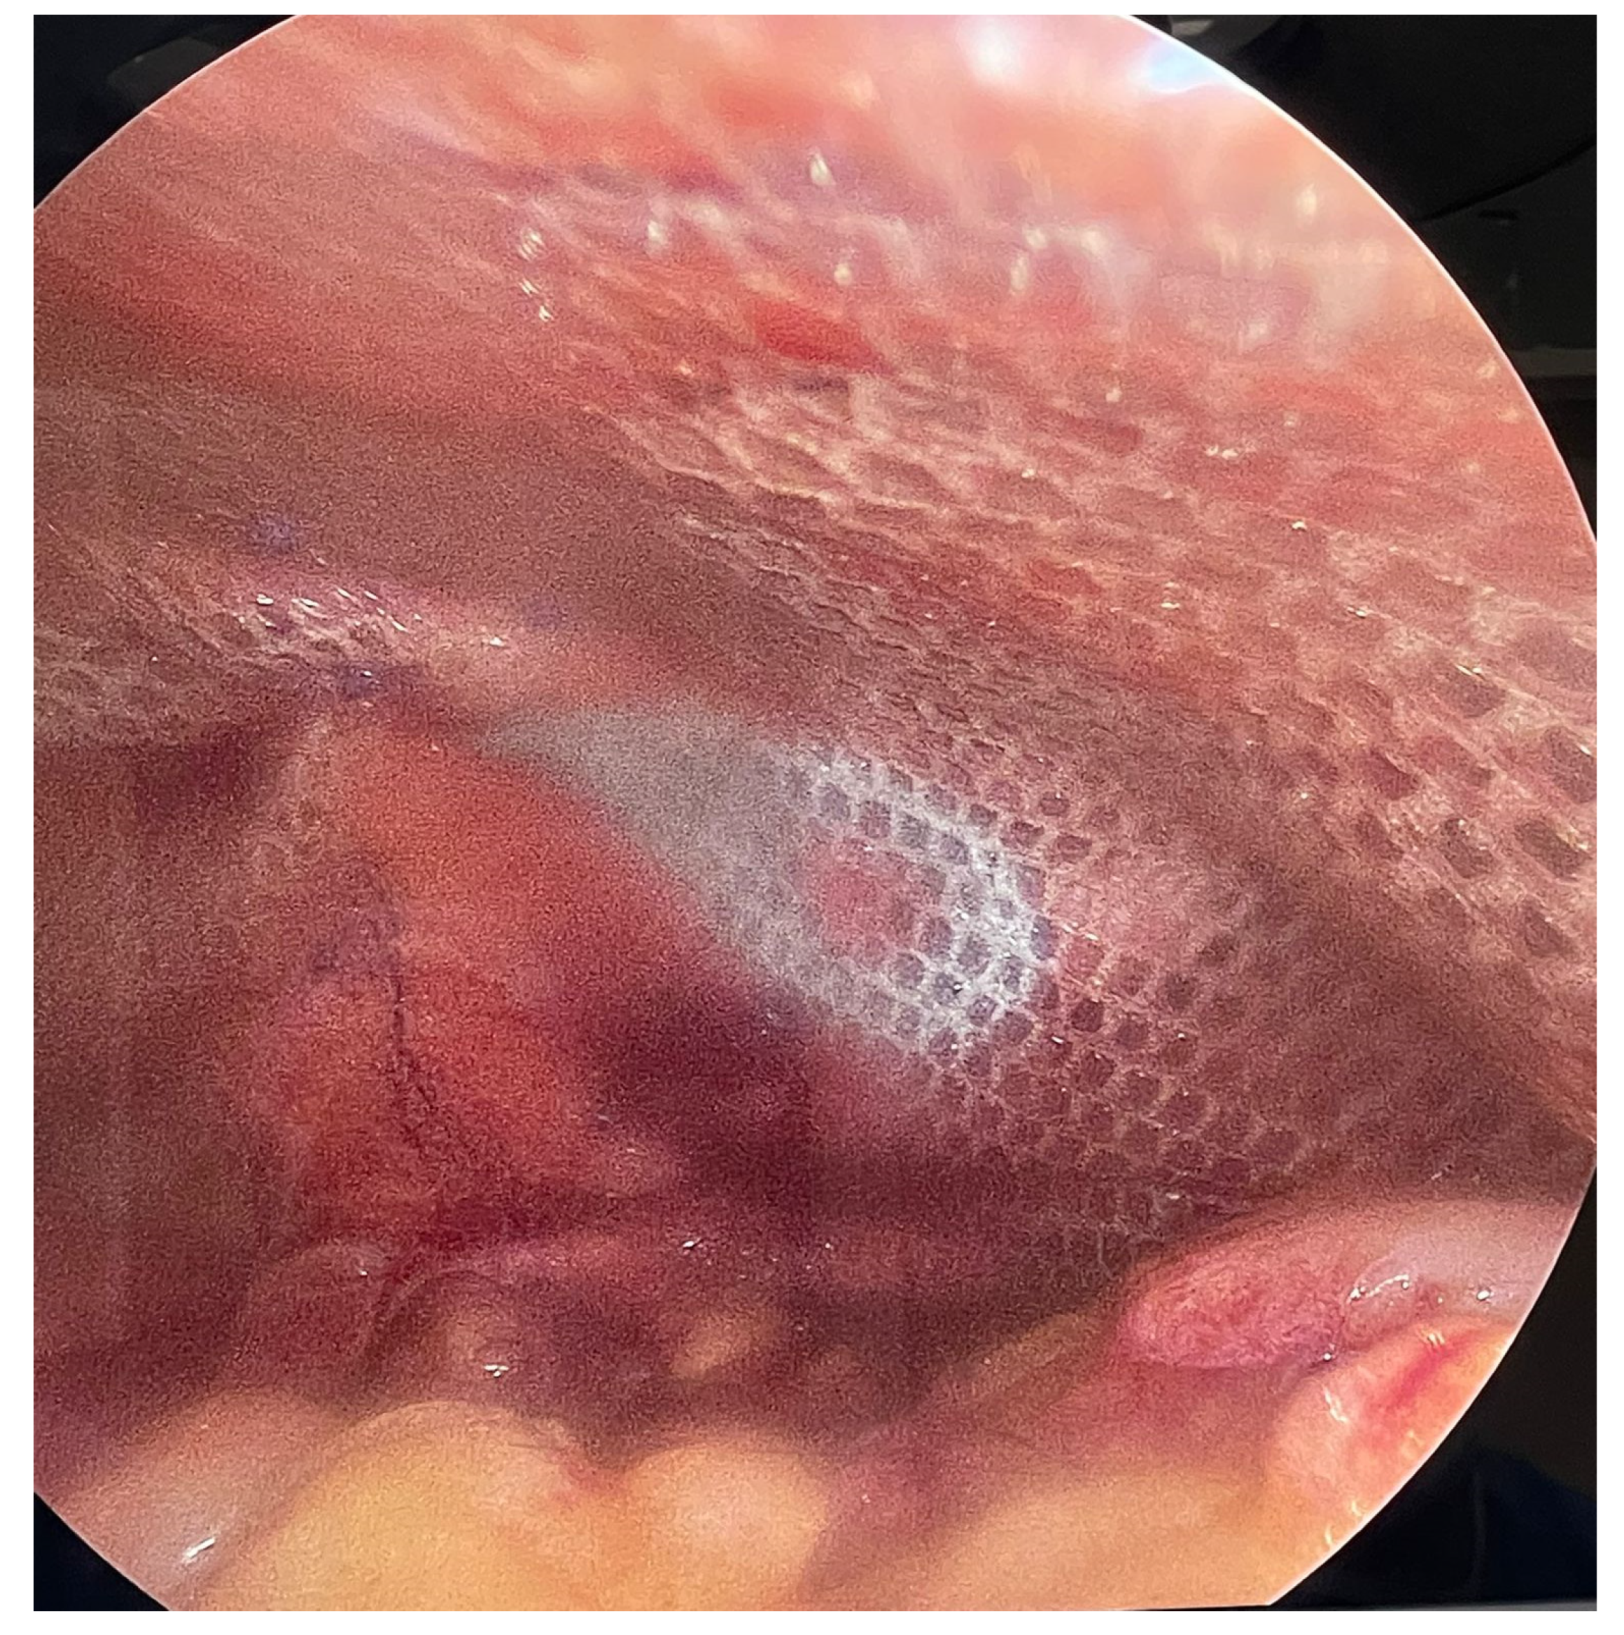

Figure 7.

Placement of the IPOM dual mesh adhered to the abdominal wall after primary hernia closure, achieving a 5 cm lateral overlap without requiring extensive incisions.